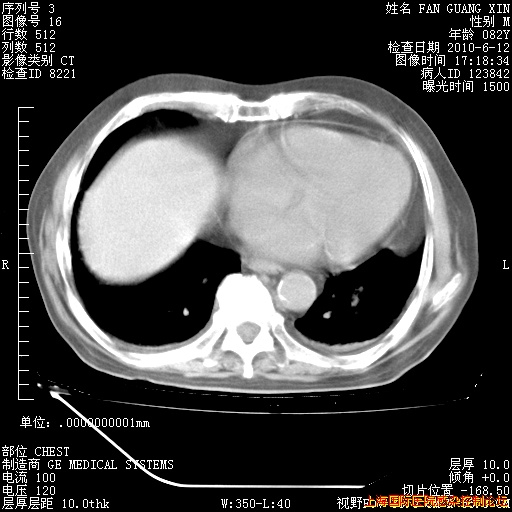

6月12日纵膈窗